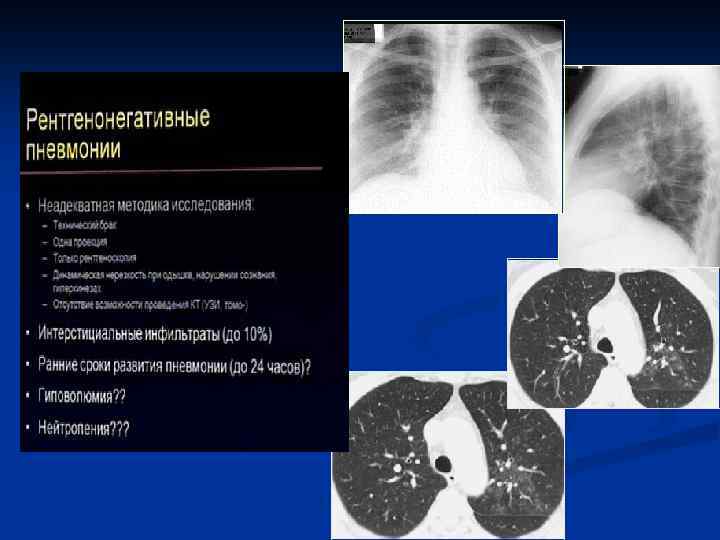

КТ–семиотика плевропневмонии – прямые признаки n n Уплотнение легочной ткани Симптом «воздушной бронхографии» Уменьшение объема Плевральные изменения

Плевропневмония

Округлой формы Отсутствие бронхов в инфильтрате